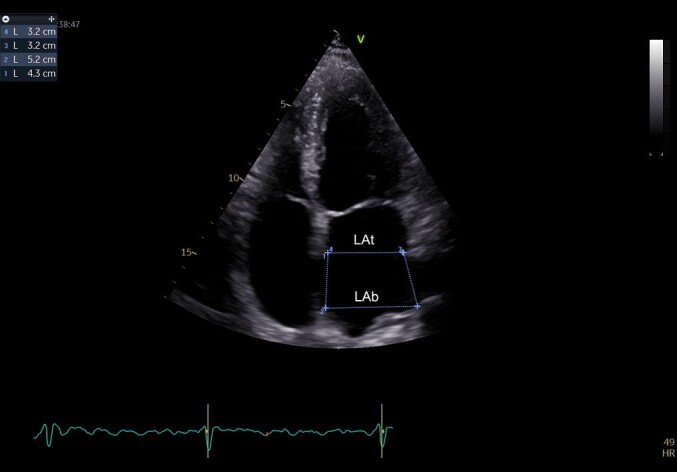

Material and methods: We performed a retrospective study in which 251 patients with AFi were included. 47 patients had an ischemic stroke before the diagnosis of AFi, at the time of diagnosis or after AFi was diagnosed. The CHA2DS2-VASc score was analyzed for all patients together with other left atrial remodeling parameters.

Results: We observed that among the patients with ischemic stroke approximately 61.70% were over 72.5 years old compared to those without stroke who presented this age in a proportion of only 44.61% (OR=2.001, P=0.0367). The CHA2DS2-VASc score had the greatest statistical impact for stroke, as expected. Patients with a CHA2DS2-VASc score >4.5 presented stroke in a proportion of 87.23% compared to CHA2DS2-VASc <4.5 who had stroke only in a proportion of 12.77% (OR=11.51, P=<0.0001). Regarding left atrial remodeling parameters, low LA ejection fraction was associated with a high percentage of stroke among patients (61.70%) compared to those with LA EF>34.5% who had stroke only in a percentage of 38.30% (OR= 2.124, P=0.0238).

Conclusions: Although the CHA2DS2-VASc score remains a good factor for predicting the association of AFi with ischemic stroke, echocardiographic parameters for the evaluation of the left atrium can be used as new risk factors for predicting the occurrence of ischemic stroke in patients with AFi.